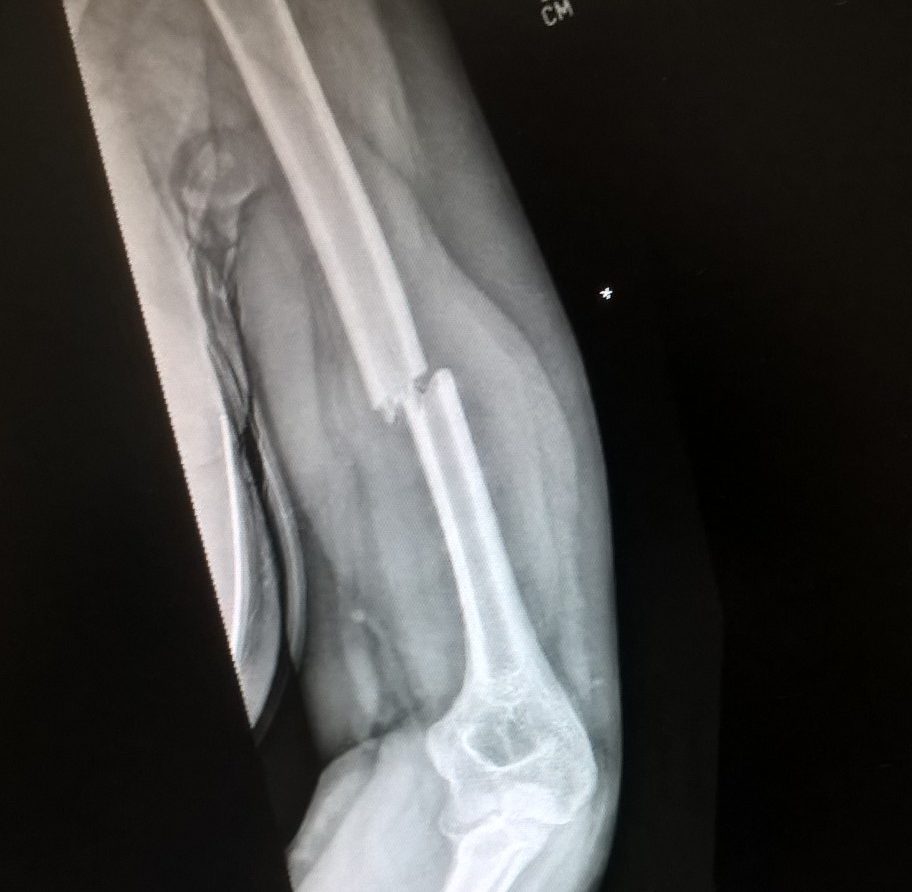

I had been really looking forward to day 17 – Thursday 20th July was my first appointment at the fracture clinic at Frimley Park. I say looking forward; I suppose there was an element of trepidation mixed in with the curiosity. I hoped I’d find out how my arm was progressing, if the bones were lining up, and above all that I’d be offered a more robust brace of some kind to give my wobbly arm more protection. I was also slightly nervous that there would be pain, that they’d try to manipulate my arm in some painful way (why, I have no idea?) or that fitting a new brace might hurt. Also that they’d look and say ‘I’m sorry, your bones are not going to meet up’. Totally irrational but that’s the nature of fear and the unknown!

In the event it was all quite quick. We were called in promptly and the doctor took a quick look and organised a chitty for an  x-ray and a brace to be fixed (relief!), promising we could come back to ask questions afterwards. We moved into the plaster room as instructed but a nurse asked me to climb into a chair with a raised armrest and I stared at in fear, saying “I don’t think I can lift my arm onto there!”. She quickly realised we were in the wrong place and the consultant came back to see us again to explain he’d only been at Frimley a week and he’d got it wrong – an x-ray today was too early to see improvement. I needed a moulded plastic brace fitting though – so we were sent off to occupational therapy to get one sorted.

Before we left I checked a few things with him – pain relief, swelling, likely timescales. I don’t think we learned anything new. He said we’d have to experiment with the pain meds to get it right, and gave 10 to 12 weeks before I’d be able to have the brace removed. He said there was a possibility the union wouldn’t be perfect but up to 30% displacement was normal and my arm would regain full functionality. I was to return in two weeks to get the update x-ray.